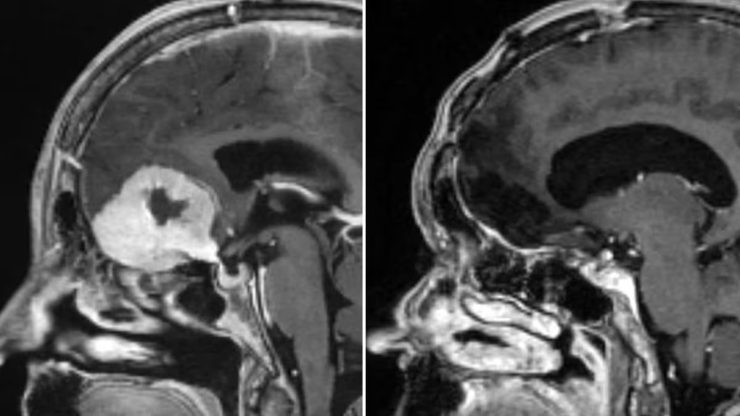

Tra i casi già trattati con successo c’è quello di Doreen Adams, una donna di 75 anni a cui era stato diagnosticato un tumore cerebrale delle dimensioni di una mela. In passato la paziente si era sottoposta a una craniotomia, senza però ottenere i risultati sperati. Con la nuova tecnica, invece, l’esito è stato diverso. “Per me la differenza tra i due interventi è stata abissale. Il mio recupero è stato molto, molto più rapido: sono uscita dall’ospedale due giorni dopo e sono tornata alla vita normale quasi immediatamente”, ha raccontato la donna.

La procedura è nata come evoluzione di un metodo già utilizzato per rimuovere alcune escrescenze craniche, che Giamouriadis ha adattato e perfezionato per il trattamento delle neoplasie cerebrali. La sua applicazione riguarda in particolare i tumori localizzati nella parte anteriore del cervello, una zona alla quale i chirurghi possono accedere direttamente attraverso il piccolo varco sopraorbitale.